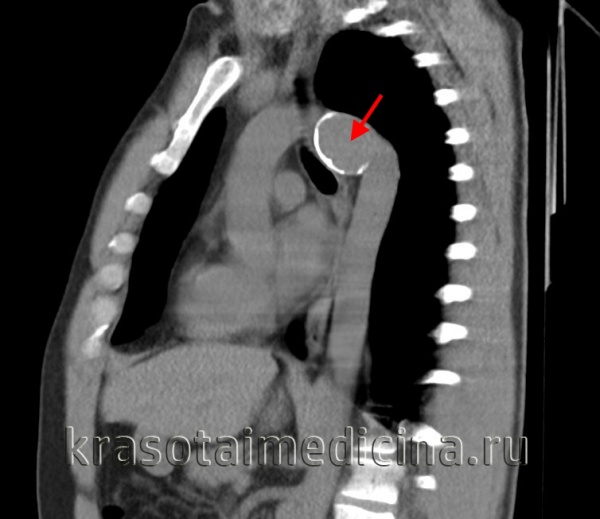

КТ-ангиография аорты. Аневризма брюшной аорты над бифуркацией. Просвет аневризмы (красная стрелка), пристеночный тромб (зеленая стрелка).